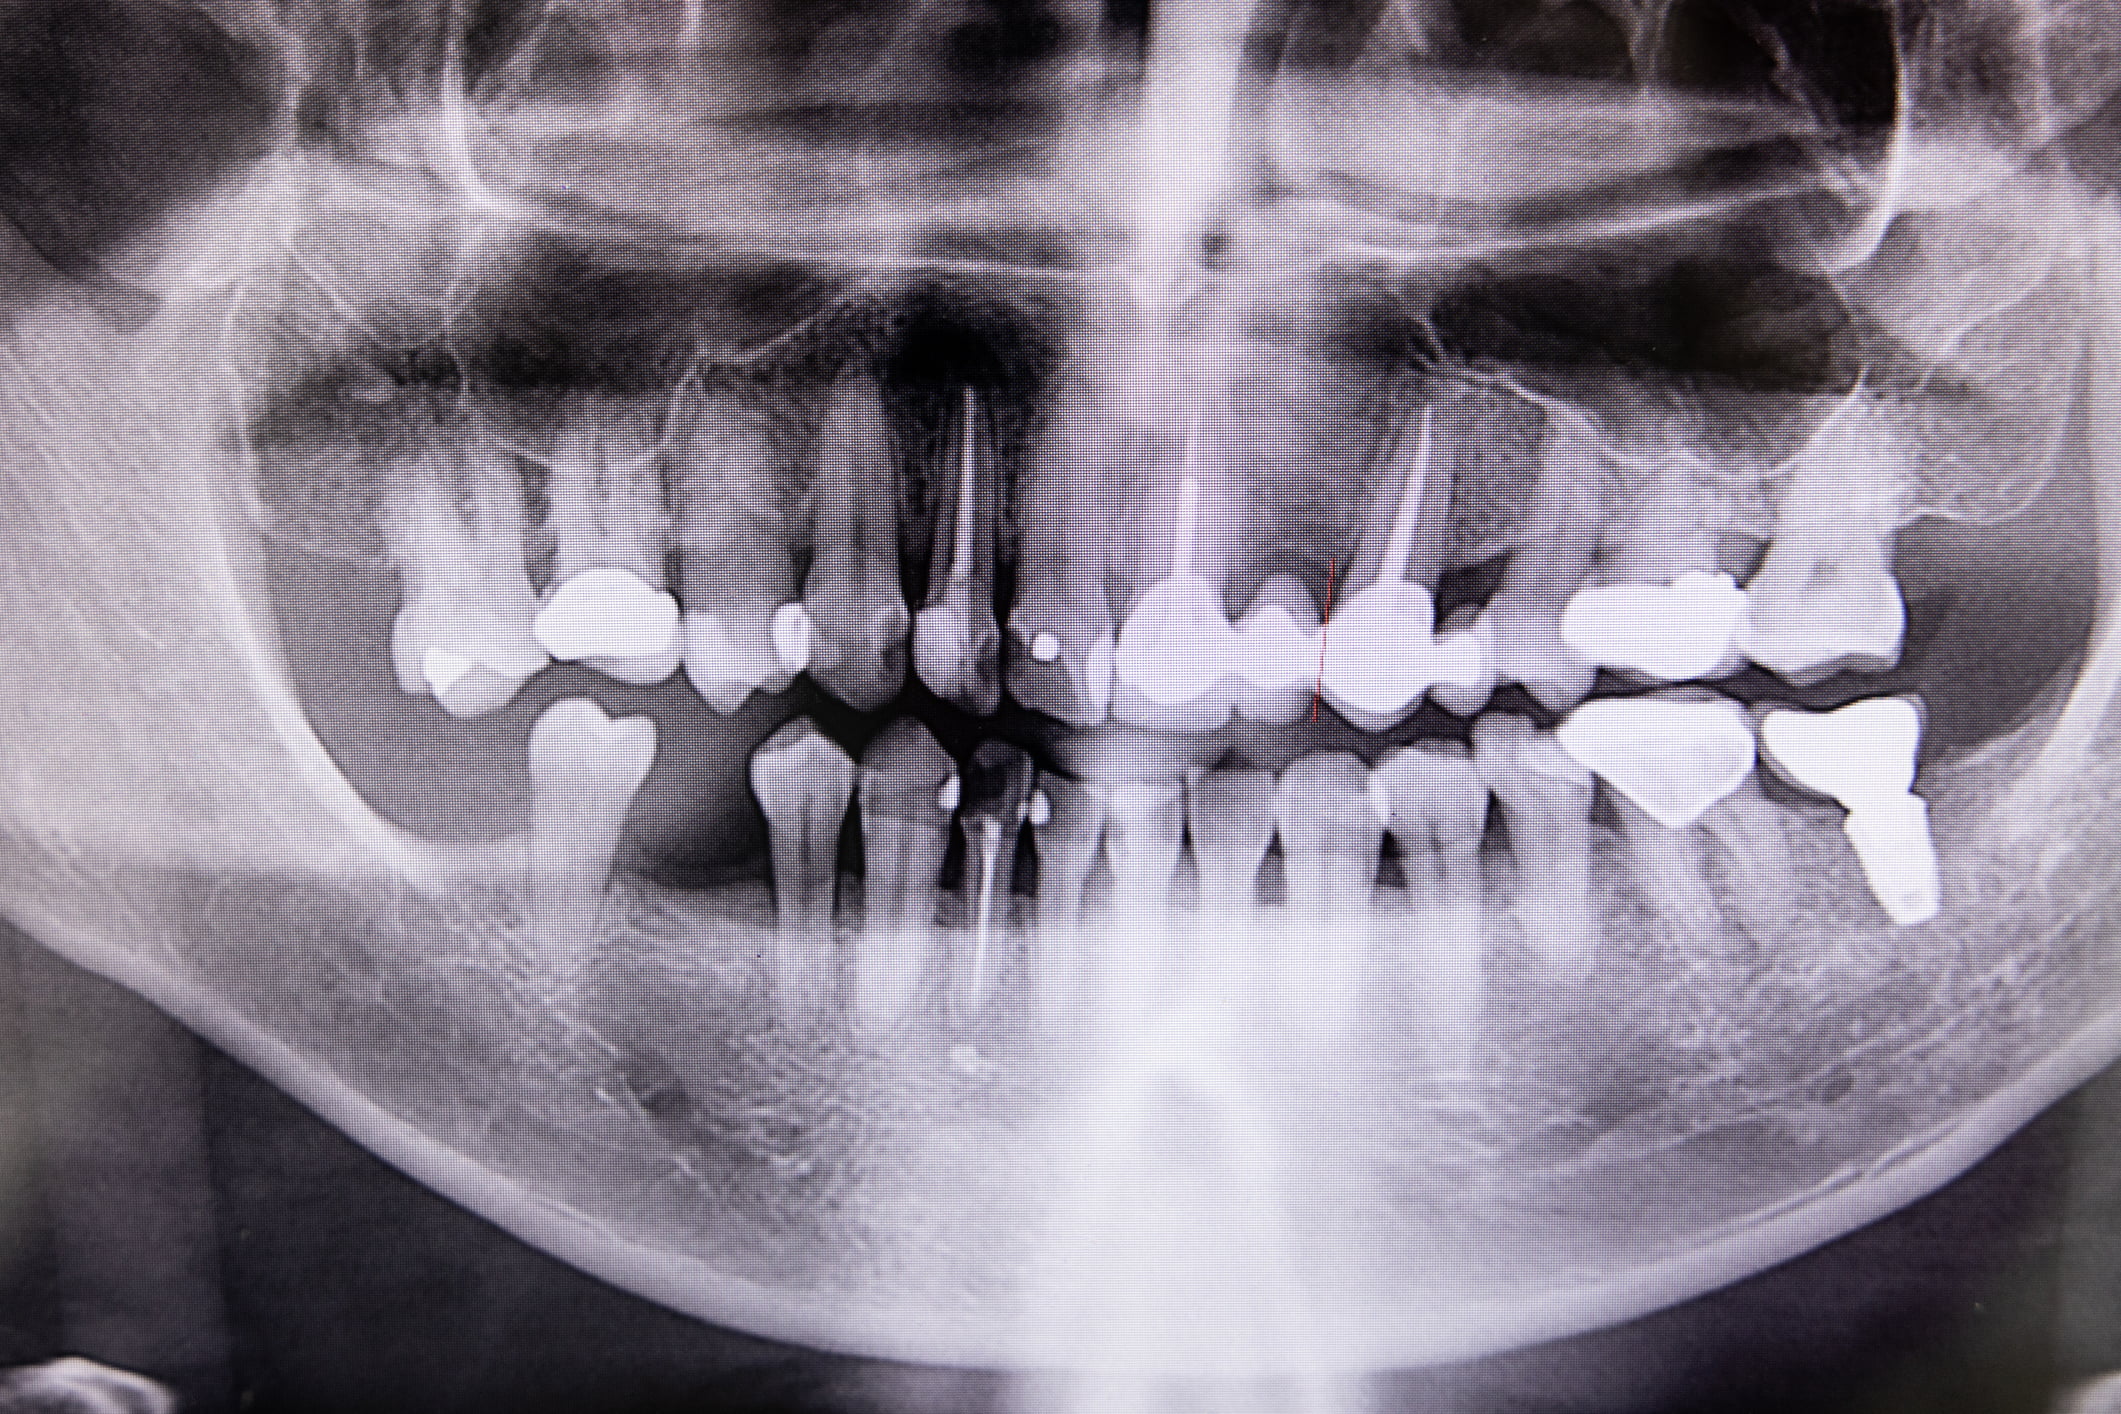

Root canal therapy, also known as endodontics, is used to prevent infection from spreading and save a natural tooth from extraction.

Root canal treatment involves removing the infected pulp tissues and resealing the tooth to help keep it protected.